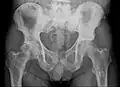

Röntgenaufnahme des Beckens eines Patienten mit Prostatakarzinom: Multiple osteoplastische Knochenmetastasen, insbesondere im Kreuzbein, aber auch im Darmbein, vor allem links (also rechts im Bild), am Sitzbeinhöcker links und im proximalen Oberschenkelknochen links. Nebenbefundlich zeigt sich eine Hüftgelenksarthrose rechts (also links im Bild). -